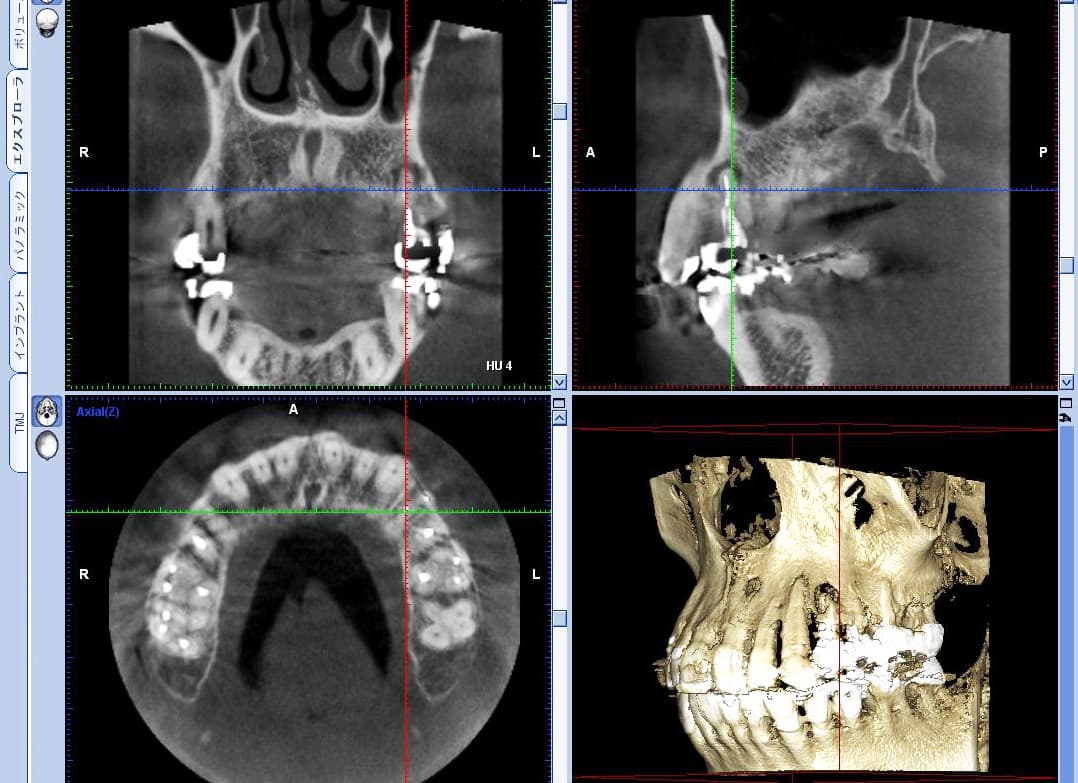

CT3Dレントゲン導入

当クリニックでは、常に最新の技術を導入し、より高度な診断と治療を提供することを目指しています。

先日新しいCTレントゲン装置を導入しました。

この装置は従来のものと比べてさらに高精度で、治療の際に必要なより詳細な画像を撮影する事が可能です。

これにより。歯科診療における診断精度が向上し、患者様への最適な説明や治療計画を建てることが出来るようになりました。

これからも安心安全、信頼度の高い治療を目指して邁進してまいります。